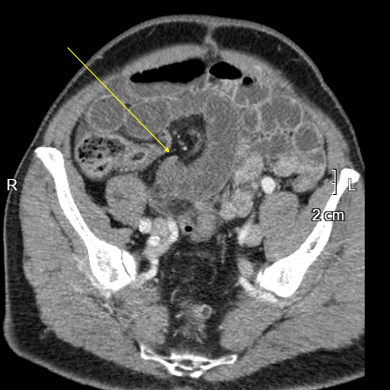

Conventional CT, oblique axial. Focus on distended bowel loop just before transition point, nothing striking about it.